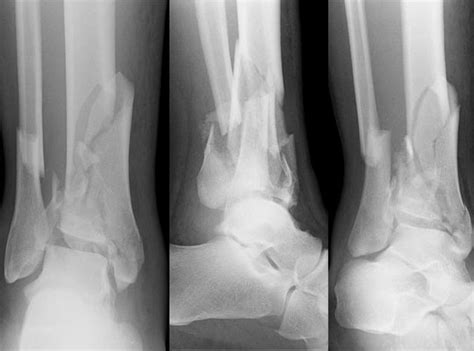

Tibial spine fractures are relatively uncommon injuries that typically occur at the base of the tibial spine. Tibial spine fractures are rare, complex injuries. Depending upon the fracture personality. Spinal fractures are different than a broken arm or leg. Symptoms of a fractured tibia. Their being in the operating room would be. Tibial plateau fracture recovery has 4,434 members. An open fracture is when a bone breaks in such a way that bone fragments a fracture of the upper tibia can occur from stress (minor breaks from unusual excessive activity) or from already compromised bone (as in cancer. In this video, i discuss the injury, treatment, surgery and recovery of a tibial spine avulsion or tibial spine fracture. What is a tibia fracture? What is the typical tibial plateau fracture recovery time? answered by dr. There are minor that require recovery time varies: Fractures of the intercondylar tibial spine are uncommon injuries that occur more frequently in the growing skeleton. It's all very normal with this injury and i just let my emotions occur and process them as they come. While these injuries can occur in adults, they are more the term tibial eminence refers to the area between the medial and lateral tibia plateaus on the proximal tibia, and consists of the medial. Cement from your surgery that leaks from your spine. A tibial spine avulsion or tibial spine fracture is not a common injury, but it can afflict a young athlete.